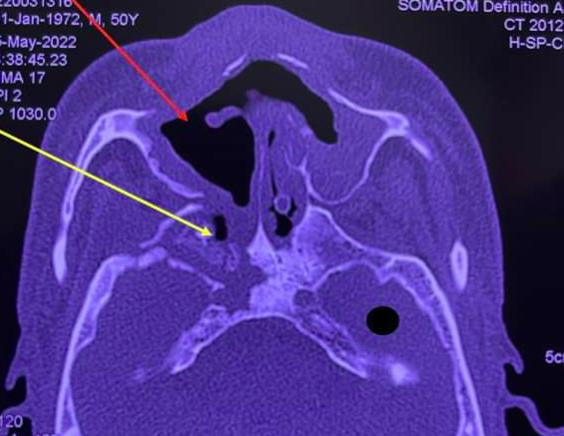

Khi xuất hiện các triệu chứng trên, cần thực hiện hội chẩn các chuyên khoa liên quan, chụp cắt lớp vi tính là phương tiện tốt nhất để chẩn đoán sớm hoại tử xương sọ - mặt. Về điều trị, cần phối hợp các chuyên khoa liên quan, phẫu thuật loại bỏ các tổ chức hoại tử.

Đặc điểm chung của các ca bệnh là từng mắc Covid-19 từ 6-8 tháng; bị đau hàm, đau răng, sưng mắt, viêm xoang. Khi vào Bệnh viện Chợ Rẫy, vùng xương sọ, xương hàm trên của bệnh nhân đã hoại tử nặng nề, phải phẫu thuật bóc toàn bộ xương chết. Nhiều bệnh nhân có mủ bám trên xương sọ, màng não hoặc ghi nhận có nấm.